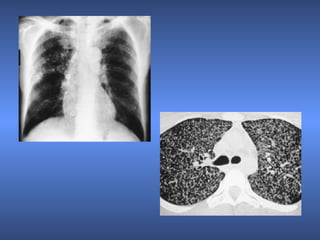

Tuberculosis pulmonar

• 1.

• 2.